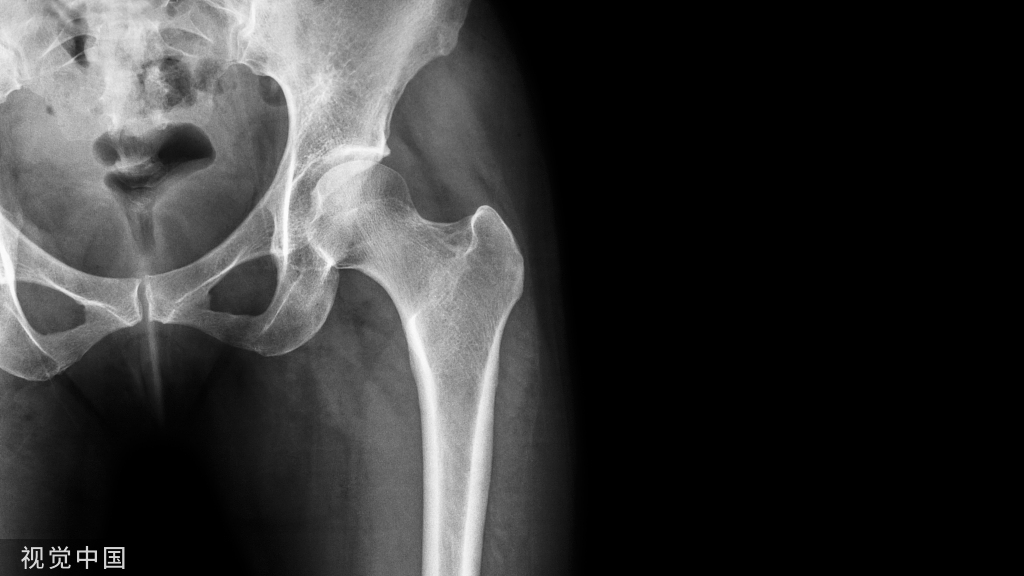

图18. 术后X线片。